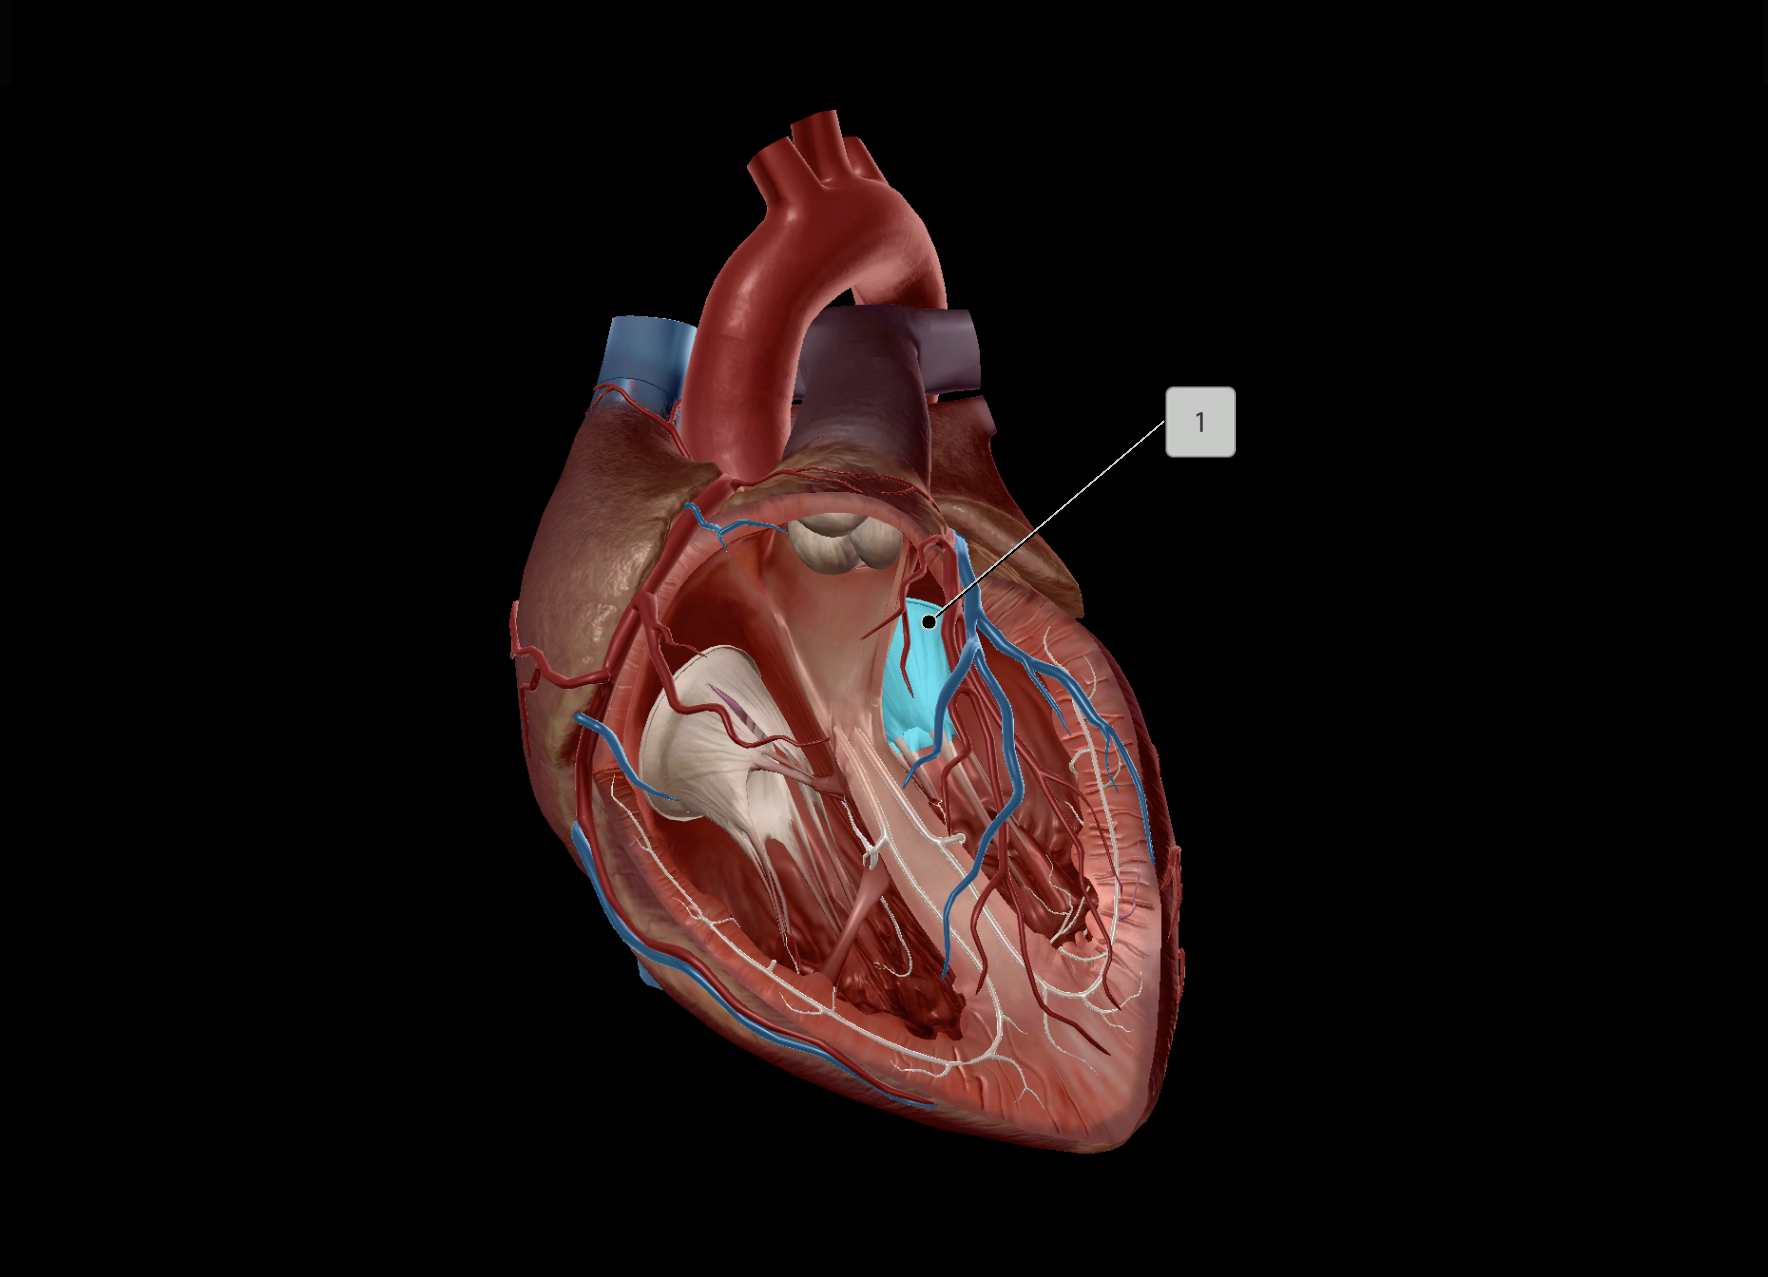

Tricuspid Valve

Bicuspid Valve

Aortic Valve

Papillary Muscle

Pulmonary Valve

Interventricular Septum

Chordae Tendineae